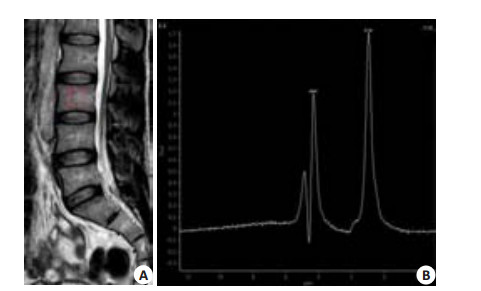

1.2 1H MRS测量腰椎脂肪含量1.5T MR行脊柱检查,采用单体素点分辨波谱法(PRESS)对L3椎体进行波谱采集,扫描参数: TR/TE:2000/42 ms;NSA:1;Voxel: 15 mm×15 mm×15 mm;Spectral Bw(Hz):1000;Flip angle: 90°;no fat/water suppression。采集数据用后处理工作站软件((Extended MR Workspace))进行测量分析。以1.3 ppm波峰为甘油三酯峰,水峰位于4.67 ppm,计算脂肪比(fat fraction, FF%)=Arealip(/ Arealip+AreaH2o)(图 1)。

图 1 L3椎体进行波谱采集 Figure 1 A: MRS of the L3 performed by PRESS and the ROI was set at the vertebral center avoiding the bone cortex; B: Water peak was at 4.67 ppm and the lip peak was at 1.3 ppm. |